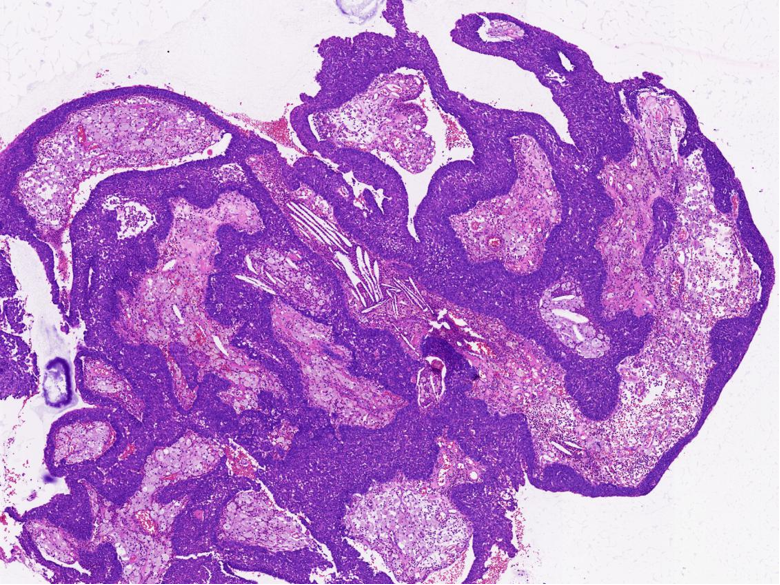

第一次手术送检:灰白碎组织一堆,合计直径1.4cm,切面灰红,质地较脆。

第二次手术送检:暗红色不整形肿块一堆,大小合计2.0cm×1.5cm×0.7cm,切面灰红,质地较脆。另送泪囊周围暗红碎组织一堆,合计直径0.5cm,质地较脆。

病理特征:宽薄乳头、 迷宫样内翻生长、单一肿瘤细胞形态、棘层松解、显著中性粒细胞浸润;

可见:细胞旋涡、透明细胞变、微囊形成、黏液纤毛上皮帽、部分肿瘤细胞异型性增加、坏死。